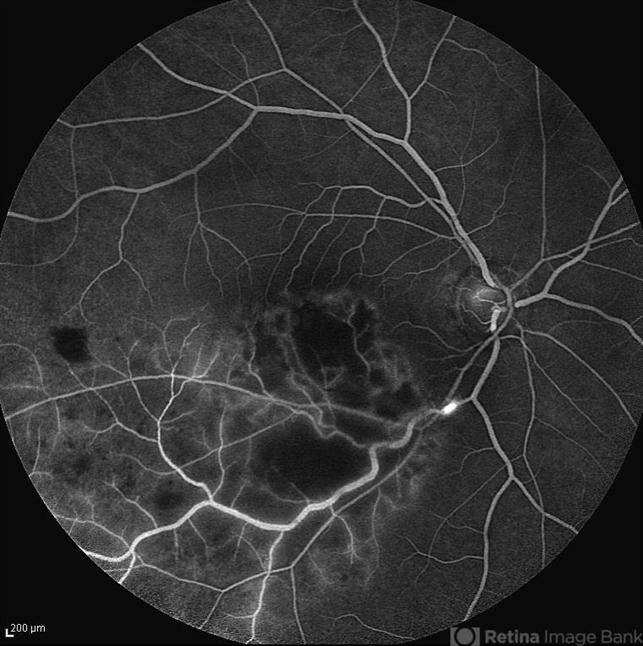

- non-perfused branch retinal vein occlusion (BRVO), macular infarction

- Late venous phase angiogram of the right eye of a 55-year-old woman with decreased vision due to BRVO. Notice capillary nonperfusion involving the macula.